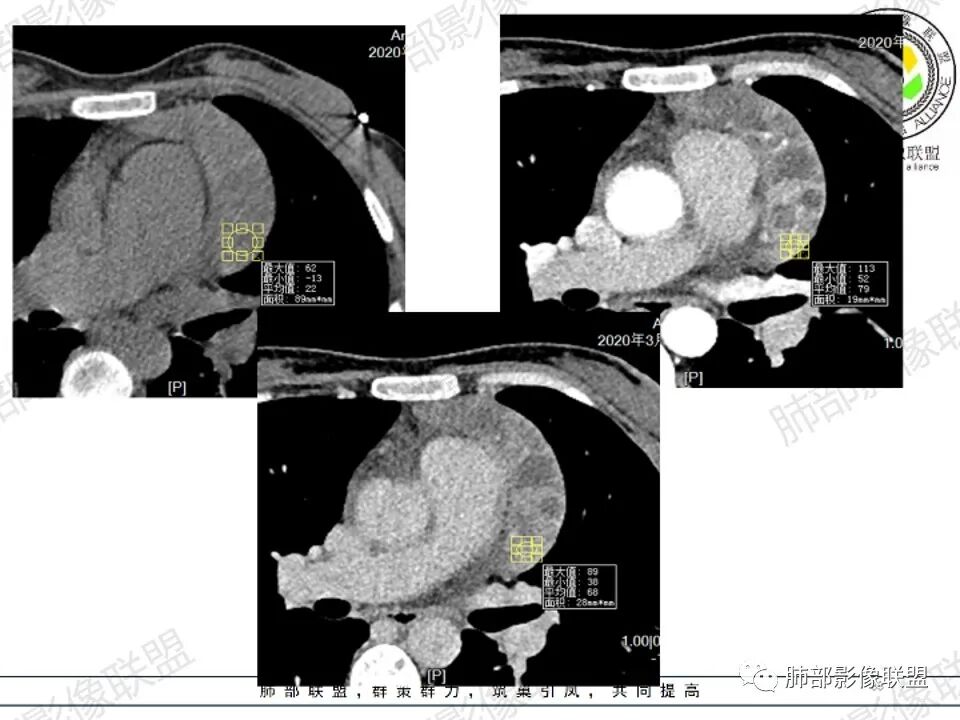

2.影像显示前纵隔不规则块状影,依势贴附心脏大血管旁,密度不均,边界不甚清楚,有结节融合感。

3.病灶轻度不均匀强化,可见血管穿行,散在液性低密度区。

双肺门未见肿大淋巴结。

4.双侧腋窝区见增大淋巴结,边界清楚。